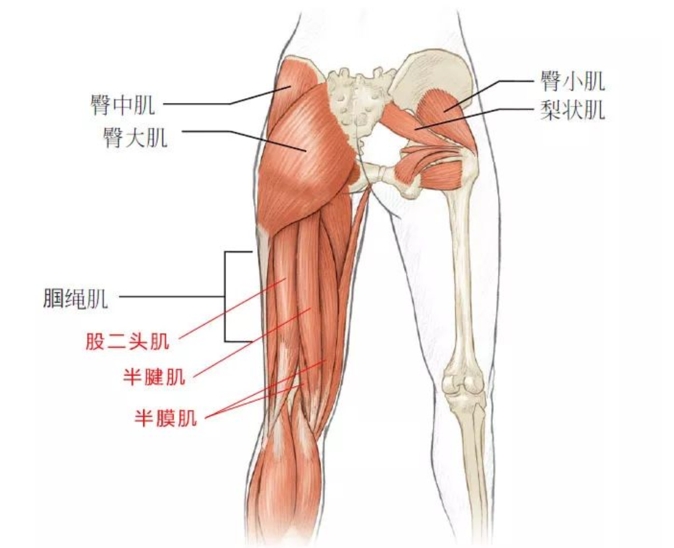

解剖学定位:腘绳肌非单一“腿筋”

所谓“腿筋”,在运动医学中特指腘绳肌群。它由股二头肌、半腱肌和半膜肌三块肌肉构成,共同负责髋关节伸展与膝关节屈曲。精准的解剖定位对后续诊断与康复至关重要。